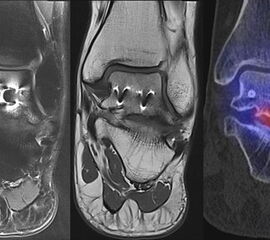

Abbildung 8.1. a bis f.: Patient mit Z. n. OSG-Distorsion vor 8 Monaten und konservativer Therapie. Anhaltende Schmerzen im Bereich des linken Innenknöchels. Im MRT bestand der Verdacht auf eine symptomatische kleine osteochondrale Läsion im medialen linken Talus (Abbildung 8.1. a und c). Zur weiteren Klärung erfolgte eine SPECT/CT 30 Tage später, welche jedoch im Gegensatz zur MRT eine fokale Mehrspeicherung an der tibialen Insertion des Deltabandes nachwies. Die Tatsache, dass die SPECT/CT spezifischer als die MRT symptomatische Bandläsionen detektieren kann wird untenstehend ausführlich thematisiert.

Abbildung 8.2. zeigt den Fall eines Patienten mit Verdacht auf ein knöchernes posteriores Impingement. Es bestanden Beschwerden dorsal bei Plantarflexion und ein Z. n. Distorsion des linken OSG vor 2,5 Jahren. Im MRT 2 Monate vor der SPECT/CT keine wegweisenden Befunde. Im SPECT/CT eindeutige fokal deutliche Mehrspeicherung im Bereich des Processus posterior tali.

Abbildung 8.3.a bis d demonstrieren Bilder einer Patientin mit Z. n. Arthrodese des linken OSG vor 6 Jahren. Das MRT ist bei ausgedehnten Metallartefakten nur bedingt aussagekräftig und weist nicht auf die auffälligen Befunde im SPECT/CT hin. Es bestehen sowohl fokale Stressreaktionen im Bereich eines Os trigonum und lateral im USG.

Abbildung 8.4.a bis d: Bilder einer Patientin mit chronischen Schmerzen im lateralen unteren Sprunggelenk links. Im MRT V. a. akzessorisches Knochenelement. Anamnestisch Beschwerden im Bereich des linken Sprunggelenkes seit 5 Monaten. Zuvor intensive sportliche Betätigung. Unter anderem tägliche atypische Belastung beider Füße durch Hinknien im Rahmen der Tätigkeit als Erzieherin. Diese Patientin hat nebenbefundlich bilaterale Akzessoria bzw. einen beiderseits angelegten Talus secundarius, der linksseitig jedoch nicht für die Symptomatik verantwortlich ist (die Bilder davon werden in Abbildung 3.5. gezeigt). Verantwortlich für die Symptomatik ist ein links posterolateral am Talus atypisches Knochenelement in einer Mulde mit engem Bezug zum unteren Sprunggelenk, DD atypisches laterales Os trigonum oder DD atypische Osteochondrosis dissecans. Die MRT konnte nicht differenzieren, wo die Schmerzursache genau lag. Im SPECT/CT (Abbildung 8.4.b und d) eindeutig fokale Mehrspeicherung im Bereich des atypischen Knochenelementes. Intraoperativ bestand der Aspekt einer Osteochondrosis dissecans.